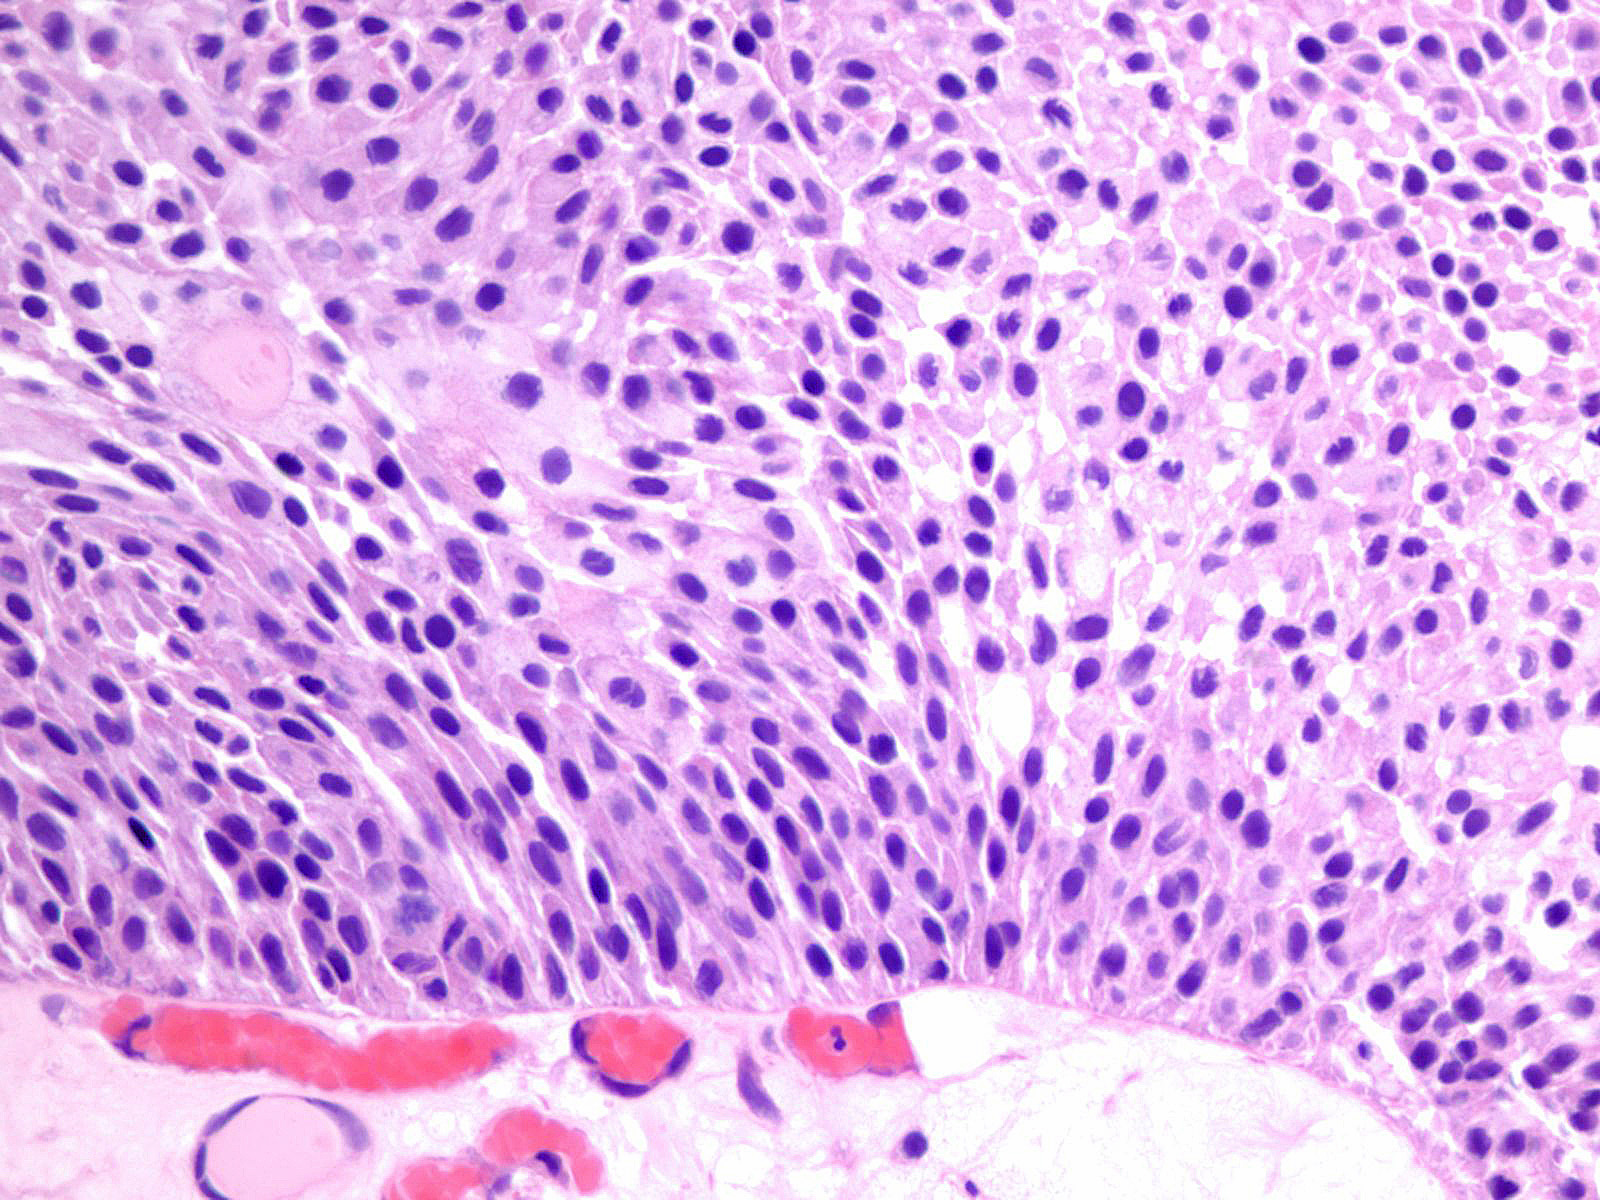

Consensus grade: Low-grade papillary urothelial carcinoma (LG-PUC)

Lesion shows moderate variation in nuclear size, shape and chromatin. Scattered nuclei are significantly enlarged and hyperchromatic relative to other nuclei. Lesion still maintains an overall orderly appearance.